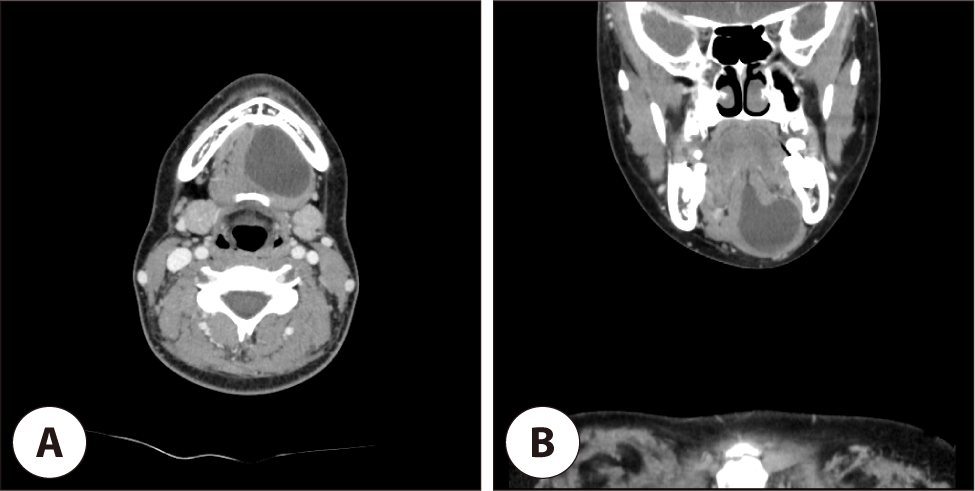

jcohns-37-1-17-g2

Fig. 2. Preoperative CT scans. Pre-operative CT scan shows about 3.7 cm well defined homogenous fluid density lesion without no significant solid portion at left side mouth floor (A) Axial CT scan. (B) coronal CT scan.

Download Original Figure

14세 여자 환자로 수년 전부터 턱 밑 종물이 있었으며 별다른 치료 없이 경과관찰 하였으나, 약 6개월 전부터 점차 크기가 증가하는 양상 보여 본원 이비인후과를 내원하였다. 특별히 호소하는 다른 증상은 없었고, 이학적 검사 상 4×3 cm 크기의 부드러운 종물이 만져졌으며 고정되어 있는 양상이었다. 내시경 상 구강저 점막은 정상 소견을 보였으며, 염증 소견 및 기타 유의미한 해부학적 변화는 관찰되지 않았다(Fig. 1A). 전산화단층촬영(computed tomography, CT) 상 3.7×3.3 cm 크기의 주위와 경계가 분명한 종괴가 관찰되었고, 일부 종괴는 하악설골근을 뚫고 아래로 전위되어 있었으며 종괴 내부는 저음영을 보이고 있었다. 조영 증강시에도 내부는 조영 증강이 되지 않는 소견이었다(Fig. 2). 임상적으로 몰입형 하마종이 의심되었으나, 수년간 지속된 턱 밑 종괴의 병력을 고려할 때 설하선 기원의 Warthin 종양 및 기타 양성 종양의 가능성을 배제할 수 없었다. 이에 질환의 감별 및 해부학적 연관성 파악을 위해 경부 자기공명영상 촬영을 시행하였다. 경부 자기공명영상(magnetic resonance imaging, MRI) 소견상 좌측 악하부에서 명확한 경계를 가진 3.1×3.3×3.7 cm 크기의 병변이 관찰되었으며, 이는 T1 및 T2 강조영상 모두에서 중등도 내지 약간의 고신호 강도를 나타내었고 유의미한 고형 성분(solid portion)은 동반하지 않았다(Fig. 3). 이러한 소견은 단백질이나 점액 함량이 높은 낭성 병변(cystic lesion)의 가능성을 시사하였으며, 고형 성분의 부재는 Warthin 종양보다는 몰입형 하마종을 좀더 시사하는 소견이었다. 몰입형 하마종 의증 하에 확진 및 치료를 위해 수술적 절제를 결정하였다. 환자 보호자가 재발률을 최소화할 수 있는 치료법을 희망함에 따라 하마종의 기원으로 추정되는 설하선을 절제하는 동시에 조대술을 시행하는 수술을 계획하였다. 구강 내 접근법을 이용하였으며 혀와 구강저의 연결부인 설소대를 따라 절개를 넣고 박리하여 종괴에 접근하였다. 구강저의 점막을 박리한 후 노출된 종괴는 육안상 일반적인 하마종의 일반적인 성상과는 달리 백색의 피막에 싸여진 부드러운 고형성 종물로 확인되었다(Fig. 4A). 술 중 설신경 및 악하선관을 확인하여 보존하였으며, 주변 조직과의 유착이나 침범 소견이 없어 설하선을 온전하게 보존하며 종괴를 완전 절제하였다. 동결절편검사는 시행하지 않았다. 환자는 수술 후 3일째 특별한 합병증이 보이지 않아 퇴원하였다.